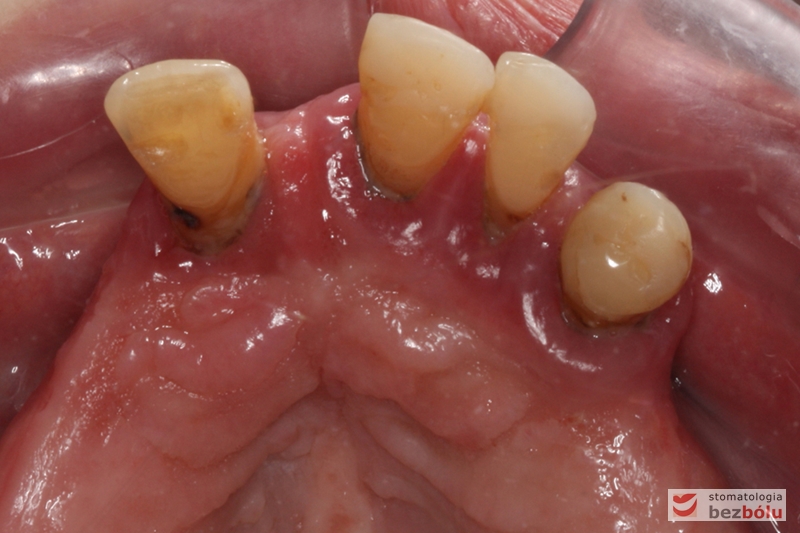

Gotowe patryce koron teleskopowych umieszczone w jamie ustnej na filarach zębów własnych